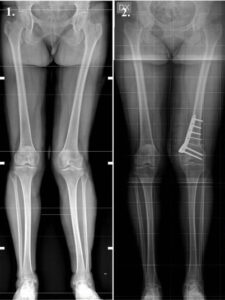

A high tibial osteotomy helps realign the knee joint. In patients suffering from knee arthritis, HTO can delay or avoid partial or total knee replacement by preserving the damaged joint tissue. Surgeons usually perform HTO to treat medial, uni-compartmental osteoarthritis of the knee and/or fix misalignment of bones that form the knee joint.

Pre and post op X-ray HTO